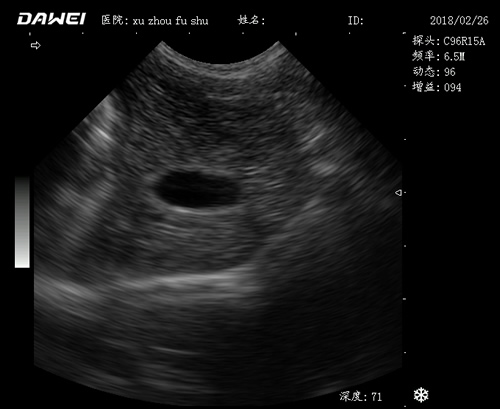

動物寵物超聲診斷儀

適用對象:

牛羊馬豬犬貓及多種家禽、實驗動物、野生動物、及部分水生動物

應用范圍:

·中小動物的肝、膽,脾、腎、膀胱、子宮、妊娠等各組織器官的檢查和病變的診斷